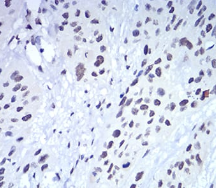

IHC    1/200 - 1/1000